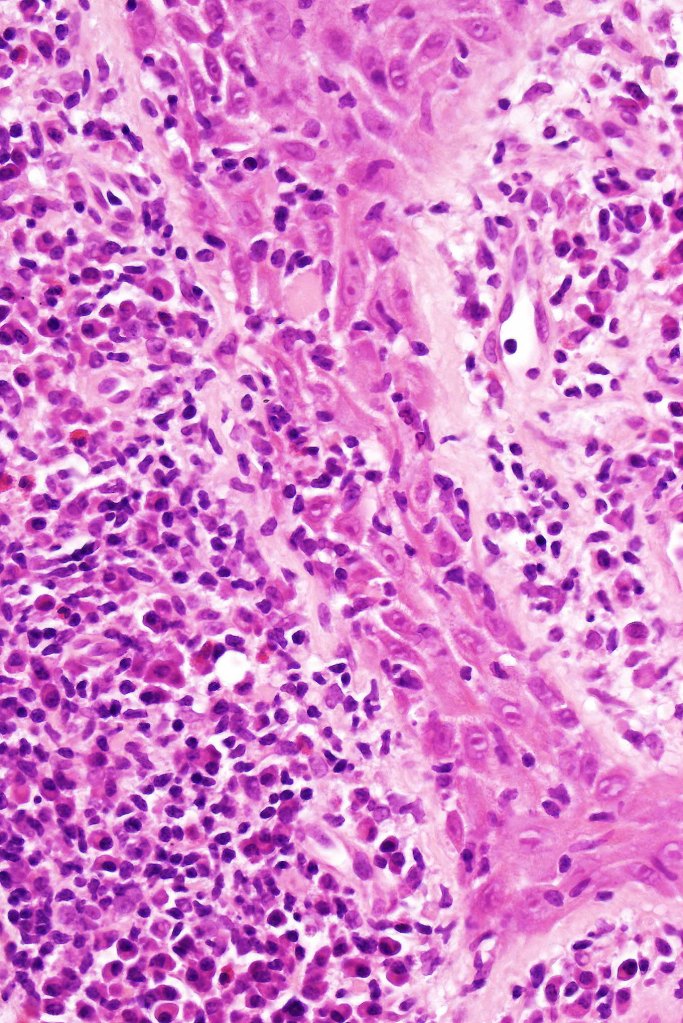

Histological features

•Follicular infiltration by atypical lymphocytes & Sézary cells

•Eosinophils sometimes conspicuous (eosinophilic folliculitis-like appearance)

•Granulomatous inflammation secondary to follicular destruction

•Large cell transformation occasionally present